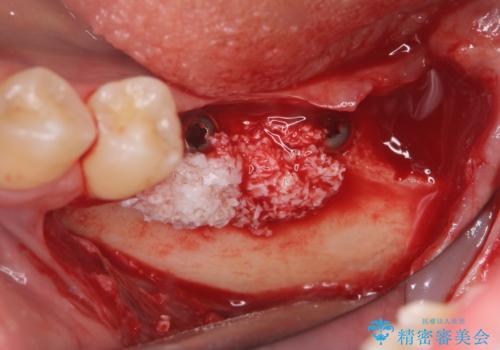

CT画像より骨の量は少なくそのままではインプラントの埋入が難しい状態です。

骨造成を行い安定したインプラントの環境を整える治療を計画します。

- 80万円(インプラント×2・骨造成・アバットメント×2)・ジルコニアクラウン×2)費用は治療当時の料金となります

インプラントの長期的な予後を見込むには、インプラント周囲の安定した十分な骨量や清掃性、角化歯肉の存在が重要です。